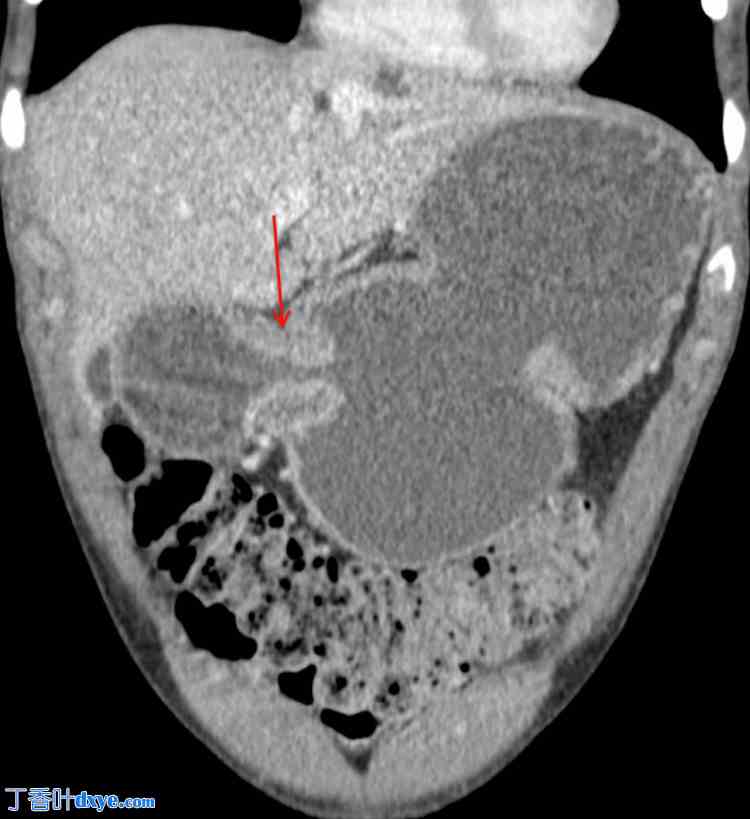

体格检查发现患者营养不良和间歇性腹胀。内镜检查和影像学检查等诊断评估证实回盲瓣和幽门管明显狭窄,并伴有纤维化狭窄和轻微活动性炎症(图1)。鉴于患者病情难治且对药物治疗反应不佳,医生认为有必要进行手术治疗。

图1. CT小肠造影(冠状位),患者胃部膨胀,幽门管狭窄(红色箭头),提示胃出口梗阻。